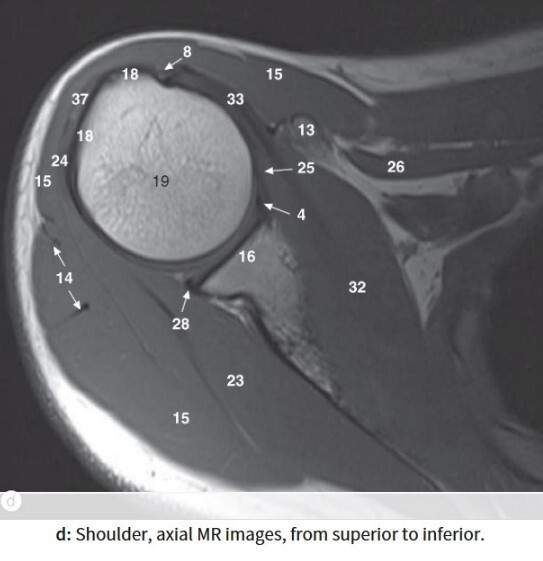

3

Q

Label 16,18,19,23

A

16=Glenoid process of Rt. scapula

18=Greater tubercle of Rt. humerus

19=Head of rt. humerus

23=Rt. infraspinatus muscle